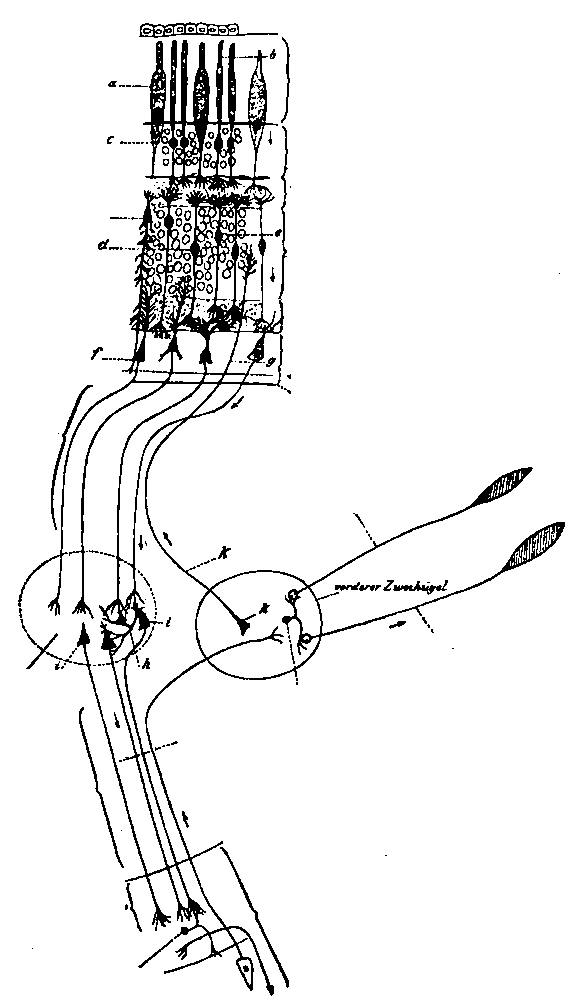

| 9. | Scheme of the visual conduction paths | 115 |

| 2. | Cortex of human brain illustrating complexity of the systems and plexuses of nerve fibers | 109 |